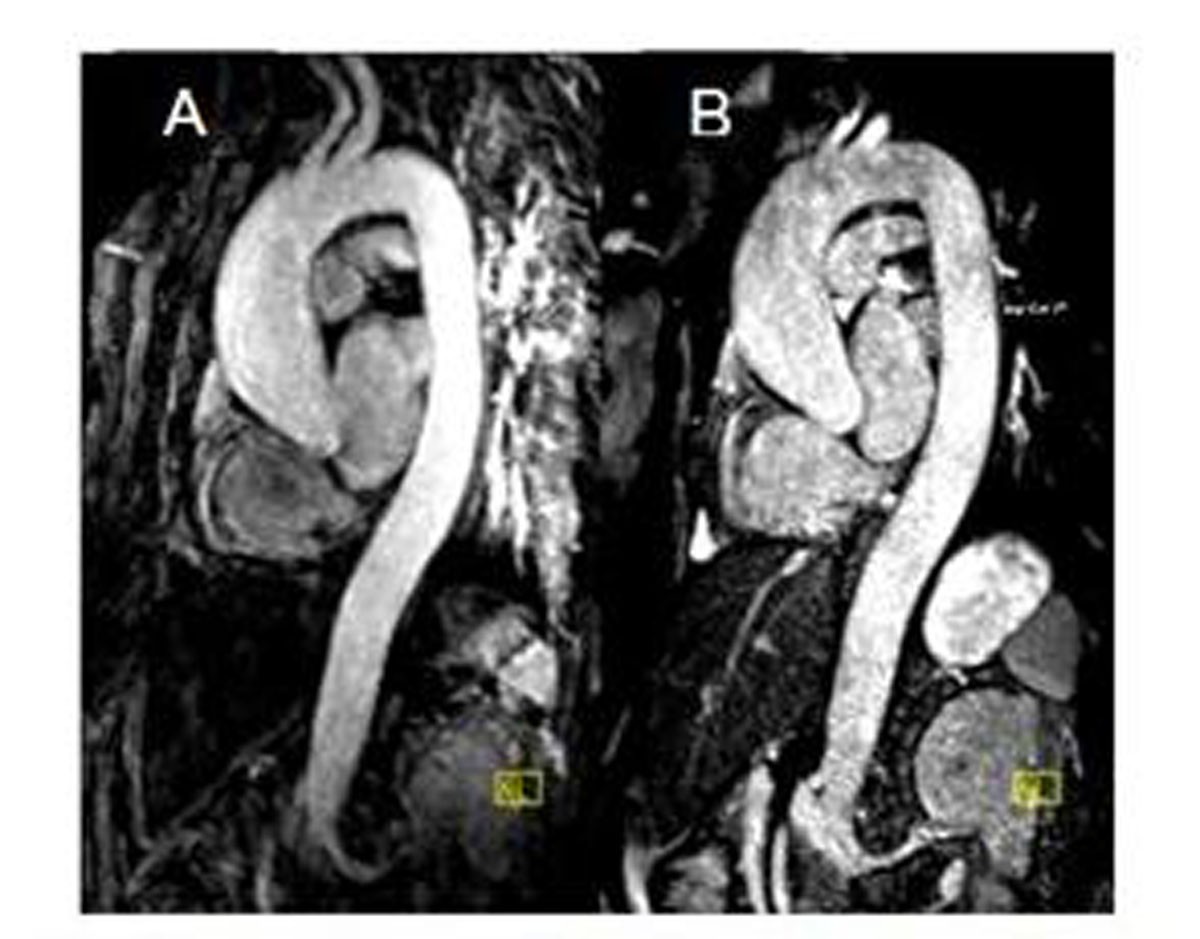

From www.researchgate.net

MRA without (a) and with contrast medium (b) in a How Does Mra Work Without Contrast unlike ct angiography, which requires the use of contrast medium, mr angiography (mra) can be performed without. during magnetic resonance angiography, you lie flat inside the magnetic resonance imaging scanner. in this review article we consider the motivations for using noncontrast mra, potential contrast mechanisms, imaging. When needed, the contrast is given with an intravenous (iv) needle.. How Does Mra Work Without Contrast.